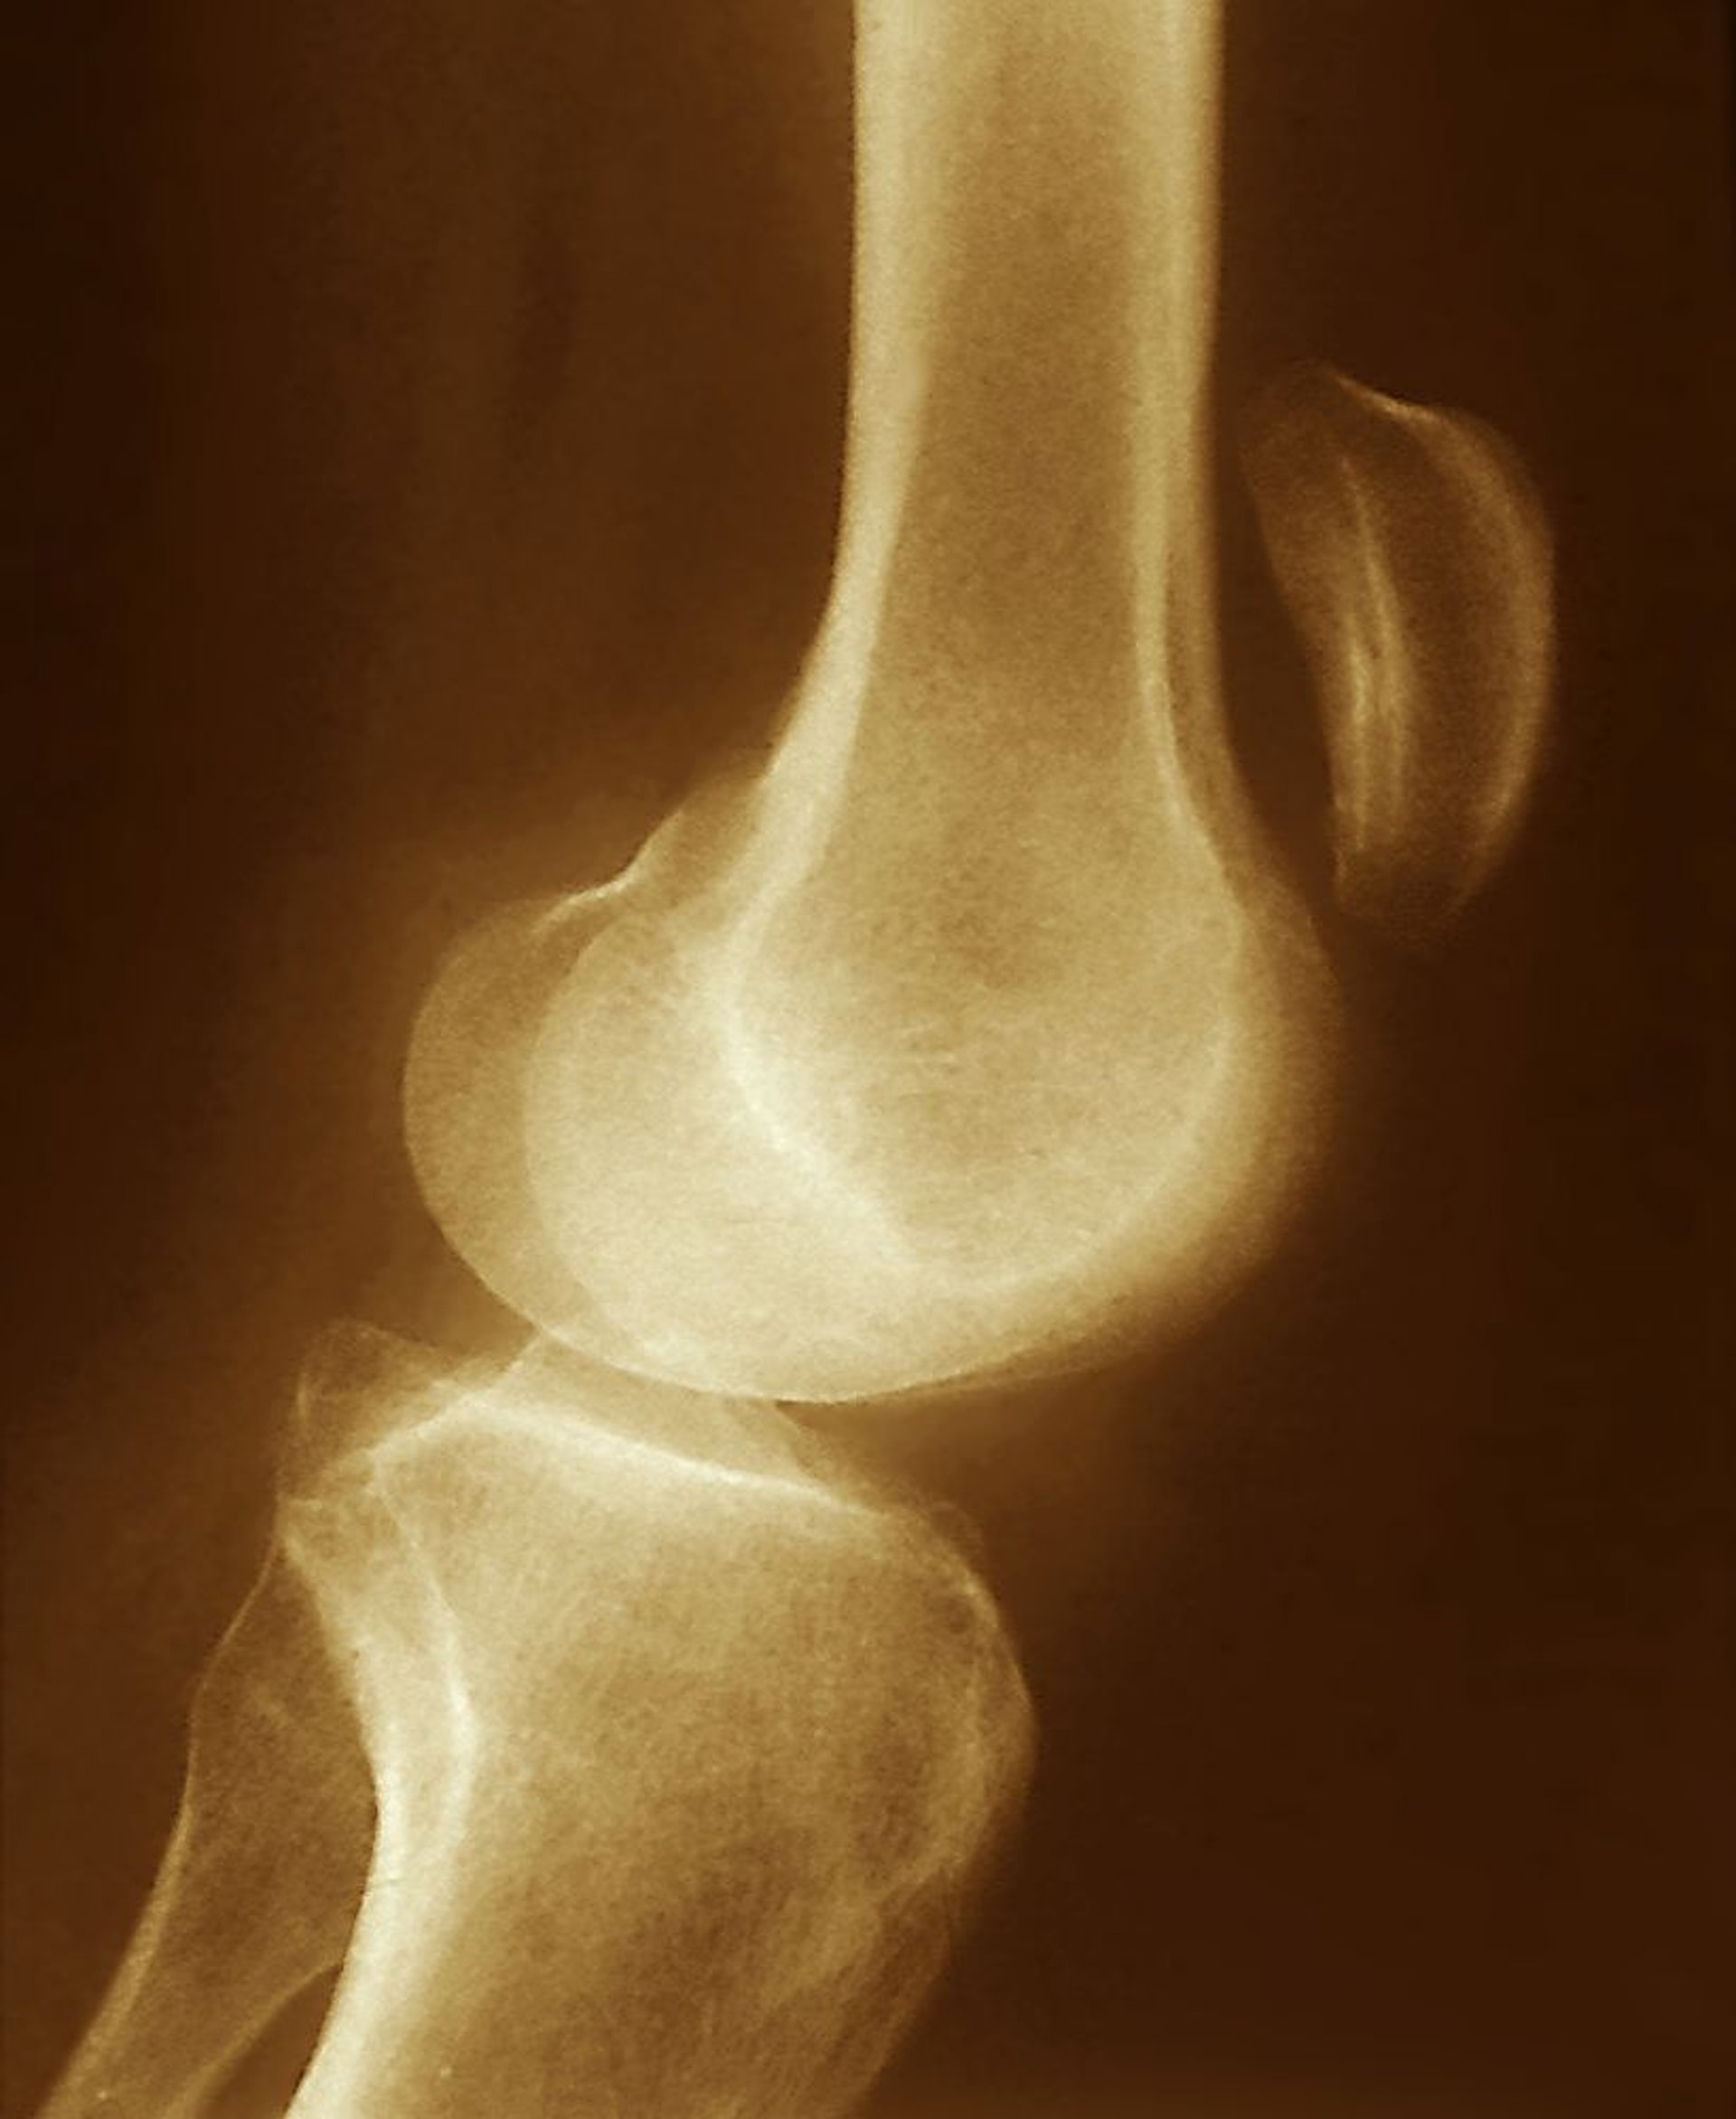

O deslocamento superior da patela observado nessa radiografia (muito acima da articulação do joelho) sugere ruptura do tendão patelar, com contração do músculo quadríceps sem oposição.

ZEPHYR/SCIENCE PHOTO LIBRARY